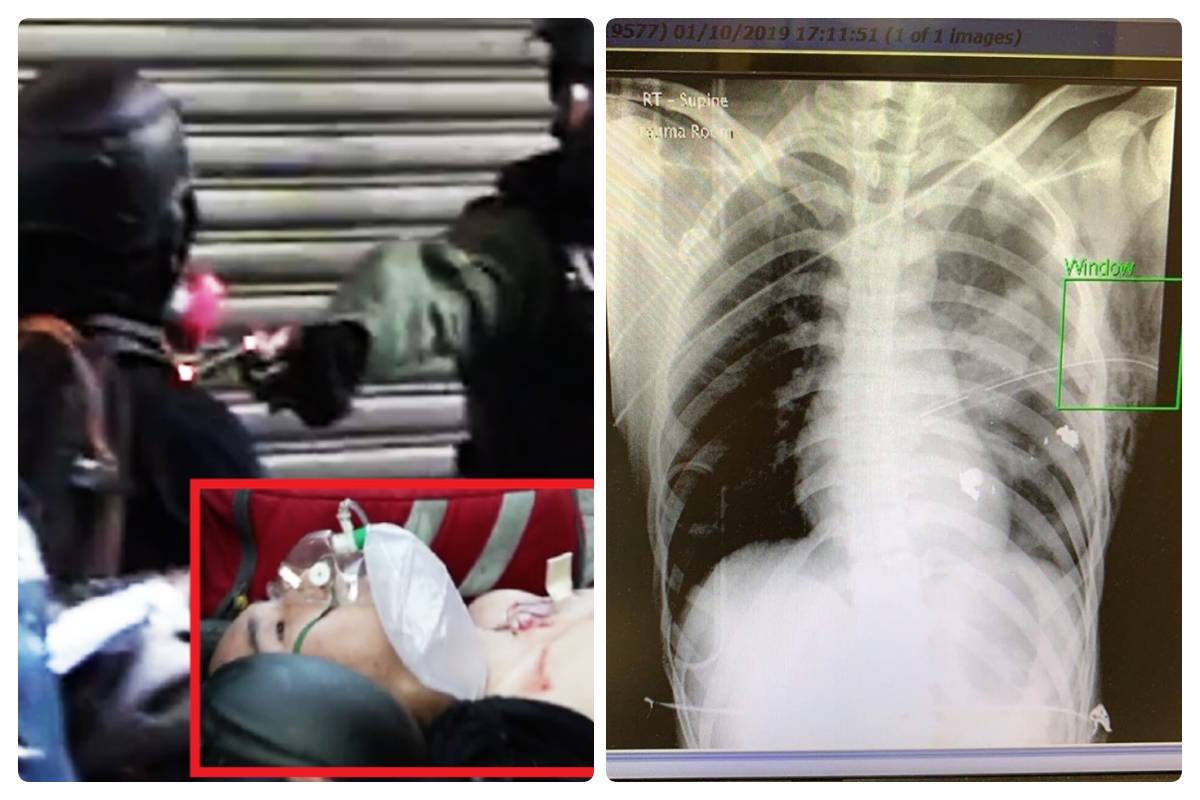

根據港大校園電視拍攝到傷者中槍畫面 ,可以看到,警方持槍朝他胸口的當下,他揮棍擊中警方的手臂,警員幾乎同一秒鐘近距離向他胸部開槍。傷者送醫後情況緊急,左肺中槍導致氣胸,一張據信是傷者的胸部 X 光片顯示,子彈碎片距離心臟只有 3 公分。

傷者的X光片(圖/擷取自TG_寶寶Channel)

對此,台大醫師姜冠宇在臉書表示,「這個孩子應該還有機會,但是後遺症很大」。姜冠宇在文中指出,轉貼的 X 光片可以看得很清楚,這是嚴重氣胸、肺已經全塌陷,並且緊急置入胸管的情況,左下角血胸的量比較少,並沒有打中肋下動脈和縱膈腔大動脈,「這是不幸中的大幸」。

姜冠宇認為,從流出的 X 光片看來,傷者應該還要再進開刀房開另一個孔,把胸管放置在更理想的位置,來解決血胸與氣胸的問題,也要胸腔鏡截去一塊在槍軌上受傷的肺葉,阻止後續可能的肺出血。